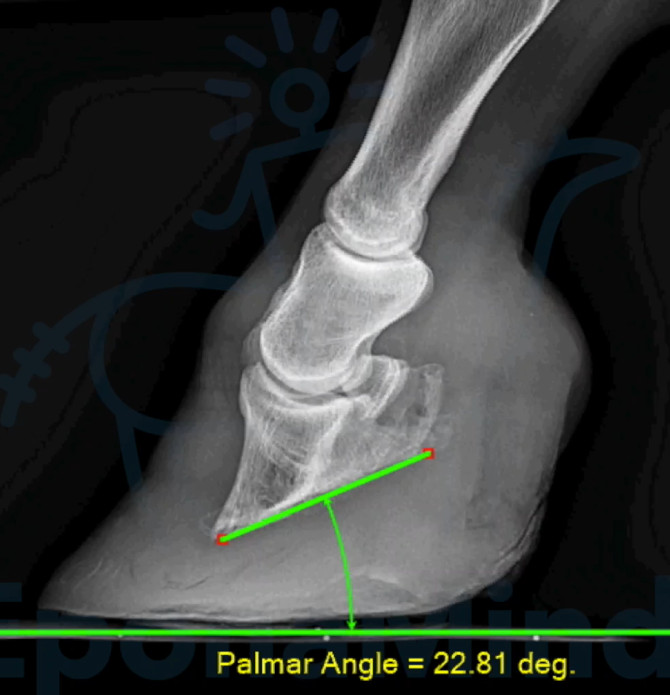

Explore a compelling case study of a horse's laminitic episode to learn practical approaches and strategies for managing this condition.

Discover the trade-offs involved in different laminitis treatment methods and identify practices that lead to the best possible results.